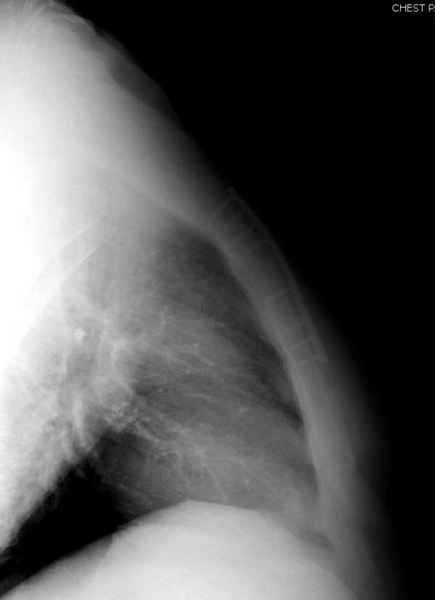

Юра, интересно, насколько такой остеосинтез контролирует степень репозиции, а то у меня имеются снимки девочки 11 лет, направленной ко мне на консультацию из одной из республик бывшего союза.

После торакальной операции, по-видимому, сильно натянули проволоку, и в результате получился захлест отломков в друг друга.

Оперировавший хирург предлагает подождать, а родителей беспокоит проблема прогрессирующей ассиметрии лица, как при кривошее.